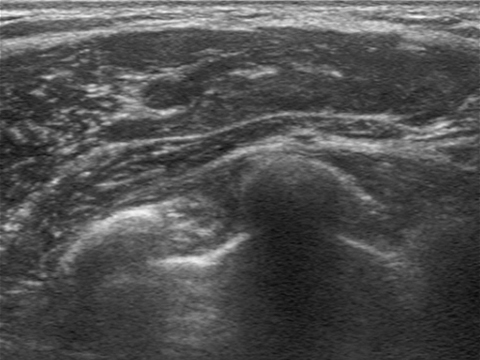

자연스러운 모양, 부드러운 촉감을 결정 짓는 요인은 바로 피막 상태!

보형물을 삽입하면 우리 몸은 이를 이물질로 인식하여

몸을 보호하기 위해 가슴을 둘러싸는 얇은 보호막인 “피막”을 형성합니다.

이 피막이 변형되거나 두꺼워지면 모양과 촉감에 이상이 생길 수 있습니다.

보형물에 맞게 얇고 균일하게 형성된 피막

비정상적으로 두껍게 형성된 피막 매우 두껍고 울퉁불퉁해진 피막

보형물을 감싸고 있는 피막의 두께가 얇게 형성된 경우

자연스러운 물방울 라인부드러운 촉감 구현이 가능합니다.